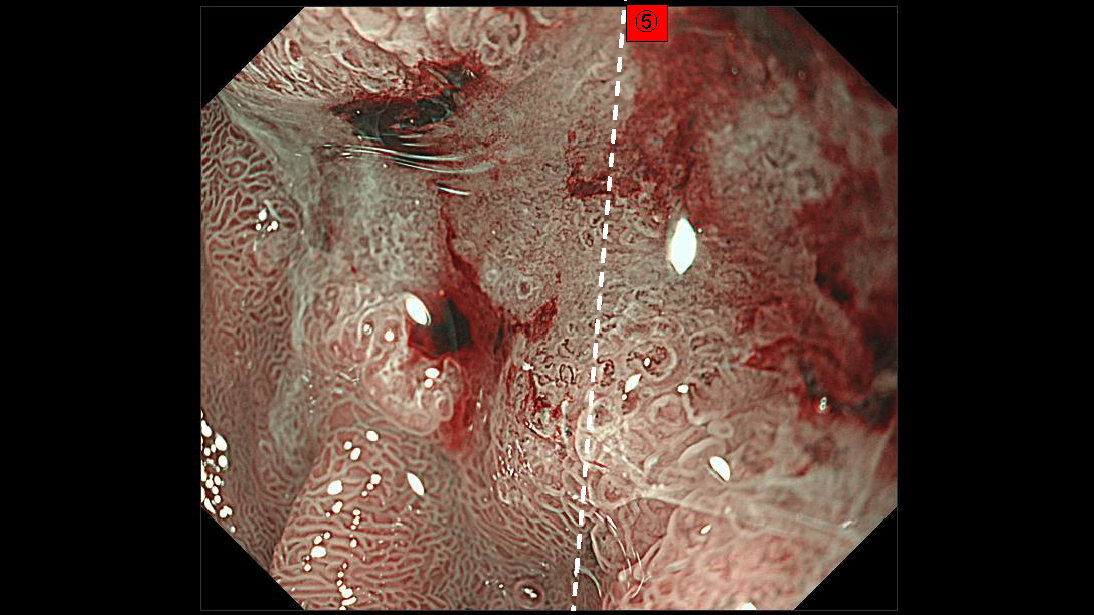

ホーム > 診療科・部門案内 > 消化器センター 消化器内科 > 消化管Mapping > 消化管Mapping~十二指腸~ > 消化管Mapping~十二指腸~ 2025.12.17